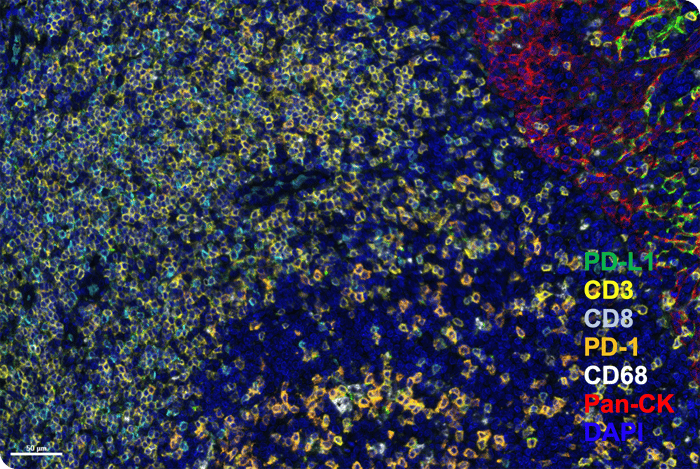

PhenoImager® HT (formerly Vectra® Polaris™) is the fastest and most highly cited whole-slide, single-cell resolution imaging platform for spatial phenotyping and the development of spatial signatures. Featuring Akoya’s patented Multispectral Imaging (MSI) and spectral unmixing technologies, this platform can be easily integrated into high-throughput workflows to accommodate projects regardless of your scale.

Figure. PD-L1-Immune Panel--Human Tonsil